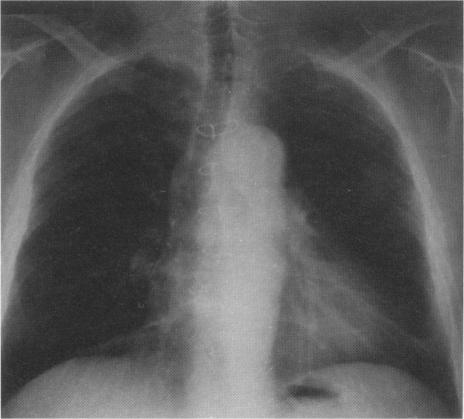

The rhodococcus is a mycobacterium-like organism which is normally a pathogen in foals. It usually spreads by direct contact or by aerosol from horse faeces and causes pyogranulomatous pulmonary infections. Occasionally, it acts opportunistically to infect immuno-compromised human hosts, most commonly those with the acquired immune deficiency syndrome (AIDS). Here we report a pulmonary infection by Rhodococcus equi in a renal transplant recipient who was successfully treated. The literature on this infection in transplant recipients is also reviewed with respect to manifestations and treatment.

马红球菌是一种类似分枝杆菌的微生物,通常是幼驹的病原体。它通常通过直接接触或由马粪便中的气溶胶传播,引起脓性肉芽肿性肺部感染。偶尔,它会机会性地感染免疫功能低下的人类宿主,最常见的是那些获得性免疫缺陷综合征(艾滋病)患者。在此,我们报告一例肾移植受者发生马红球菌肺部感染并成功治愈的病例。同时,我们还就移植受者中这种感染的表现和治疗对相关文献进行了综述。